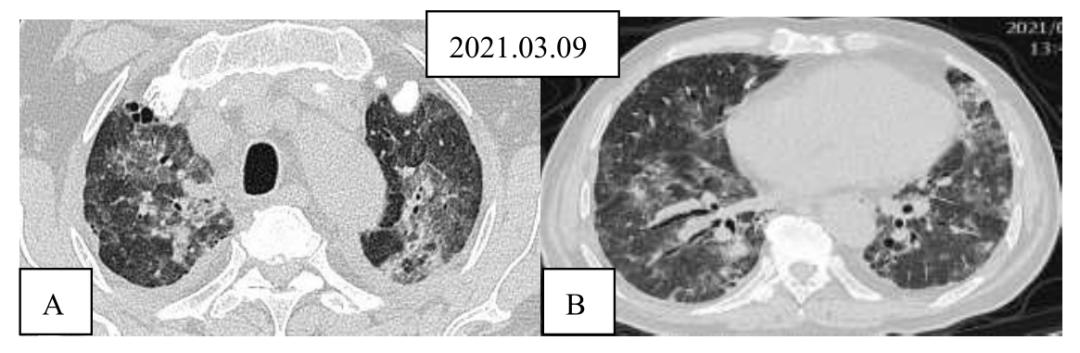

胸部高分辨率CT(2021年3月9日)

图1激素治疗前胸部CT平扫图A(矢状位)及B(冠状位)示双肺弥漫性磨玻璃影,双下肺可见牵拉性支气管扩张。诊疗经过

图3激素治疗前后胸部CT平扫对比图上行,激素治疗前主动脉弓(A)及下肺静脉(B)层面CT表现;下行,激素治疗1周后,主动脉弓(C)及下肺静脉(D)层面CT,示双肺磨玻璃影较前明显吸收。5.手术:经治疗10天,患者已无明显活动后气促。复查血气分析,患者呼吸空气时,PaO2可达85 mmHg。激素治疗已减量为口服强的松30 mg/日。患者转回骨关节科,2021.03.26在全麻下行右侧髋关节滑膜切除术+右侧髋关节松解术+右侧髋关节置换术,术后恢复良好。

答:基于人群的研究显示,约5%-10%的RA病例发生临床明显的ILD。RA-ILD中UIP为主要病理类型(56%),其次为NSIP(33%),机化性肺炎(11%)[1]。从影像学特征分析,RA-ILD阳性患者常见的肺部改变是网格样改变(57.8%),胸膜增厚(57%),磨玻璃样改变(53.2%)。与RA-ILD阴性患者相比,RA-ILD阳性患者出现胸膜增厚(57.0% vs. 28.1%),支气管扩张(18.1% vs. 10.5%),支气管血管束增粗(35.4% vs. 9.6%)和肺动脉高压(9.4% vs. 3.6%)的比例明显增加,两组相比出现肺大泡、肺部结节和胸膜下结节的比例则没有统计学差异。这名患者的胸部CT扫描显示主要为双肺磨玻璃影,病灶沿气道累及更明显,双下肺有支气管扩张改变,而无典型蜂窝。此外,患者激素治疗后短期内病灶吸收。这些特征都不同于典型RA-ILD的特征。